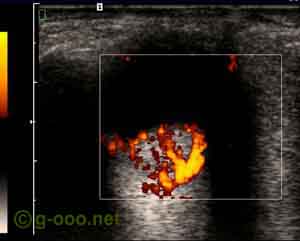

Hemangioma da coroideia do polo posterior do olho esquerdo, de uma mulher.

Aspecto da ecografia Doppler (power Doppler), que revela intensa circulação interna.